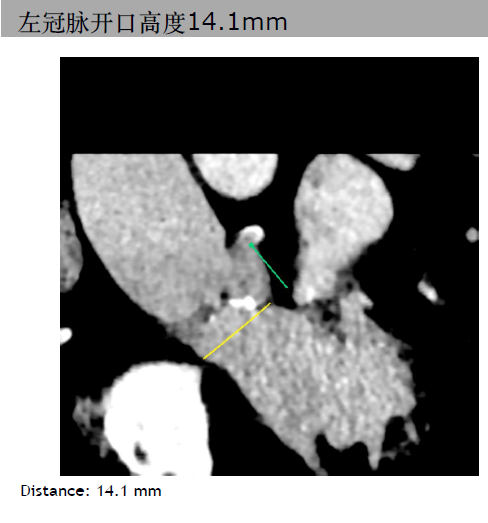

三叶瓣,主动脉瓣环平均直径21.3mm。右冠脉高度10.3mm,右窦直径:28.4mm。左冠脉高度14.1mm,左窦直径:30.4mm。STJ平均直径25.4mm,高度17mm。